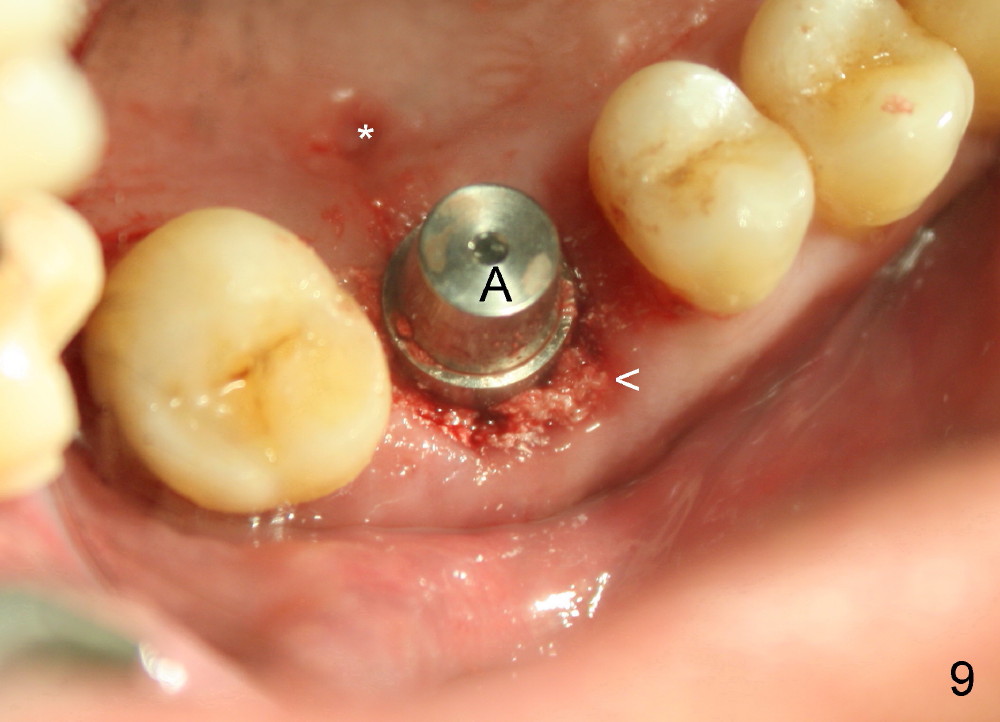

The upper right 1st molar of a 48-year-old man has severe perio endo disease (Fig.1 #3); the bone height for immediate implant (Fig.2) is about 3.5 mm (Fig.1 vertical line). There is a buccal (Fig.3 B) abscess (*); the palatal (Fig.4 P) root is exposed. After extraction, the socket available for immediate implant (Fig.5,6 S) is buccal (without septum), whereas the apex of the palatal root is far away from the main socket. In fact there is an advantage: the socket is smaller. Osteotomy is created in the main socket as palatal as possible, using osteotomes, reamers and taps (Fig.7 T). The sinus floor is lifted (Fig.7 ^). When 7x17 mm implant is placed (Fig.8 I), the insertion torque is >60 Ncm. The remaining socket (Fig.8 *) is to be packed with mixture of autogenous bone, allograft and synthetic bone (Osteogen) (Fig.9,10 <). Immediate insertion of an abutment (Fig.8-10 A) helps retain perio dressing (Fig.11,12). No collagen membrane is used in this case to cover the bone graft before placement of perio dressing. Postop the patient cannot tolerate oral Amoxicillin because of stomach upset. The dose is reduced. Two weeks postop, the perio dressing is stable, but discolors (Fig.13). When the dressing is removed, the buccal bone graft is exposed, which is not abnormal. What is unusual is discoloration (Fig.14). The significance of the latter is not revealed until 3 months postop when the patient remains asymptomatic, but there is an apical fistula (Fig.15 <). There is a communication between the fistula and the buccal sulcus of the implant: water passing freely. Based on the position of the buccal plate of the neighboring teeth (*), the buccal plate of the implant should be lost, which is consistent with finding of PA (Fig.16, as compared to Fig.8). Guided bone regeneration seems necessary.